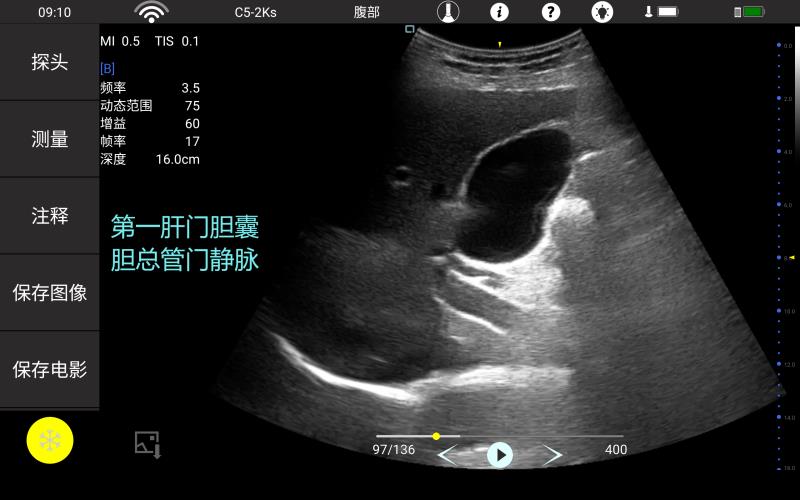

• 大凸

腹部

肾脏

妇科产科

心脏

肺等